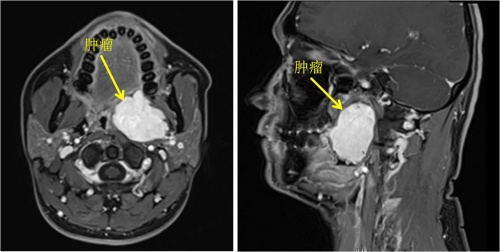

岳阳33岁的李先生最近总感觉咽部不适,而且一张嘴就能看到左侧颈部凸起一个肿块,到医院检查发现咽旁间隙藏着一个46mm×38mm×52mm的肿物。这个潜伏的“炸弹”不仅位置深,还血供丰富,已压迫周围组织,若不及时处理,可能堵塞气道、累及重要神经血管,危及生命。

李先生连忙到捷克论坛 耳鼻咽喉头颈外科三病区就诊,接诊的周建波主任医师表示,咽旁间隙是上接颅底、下连颈部的“危险三角区”,密布着颈动脉、颈内静脉、迷走神经等关键结构,手术稍有不慎就可能引发大出血、神经麻痹、甚至声嘶、吞咽障碍等,风险极高,而李先生的肿物位置较深,又紧邻重要结构,手术难度超乎常规。传统手术需从颈部开刀,不仅会留下明显疤痕,还可能因视野限制增加神经血管损伤风险。